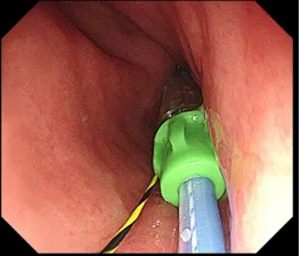

▲ 通过导丝植入支架